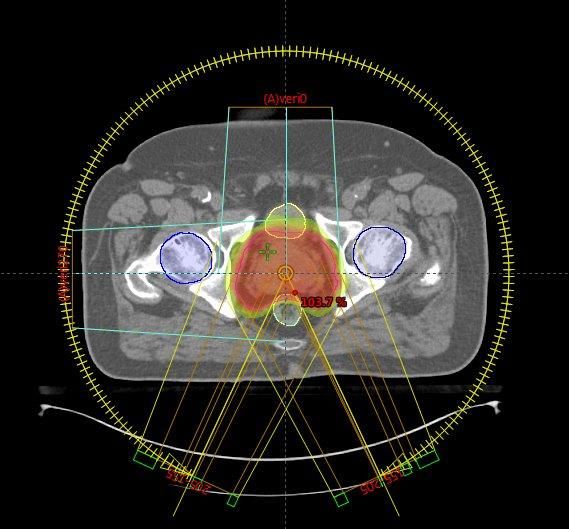

Prostatakrebs

Die Behandlung von Patienten mit Prostatakrebs erfolgt üblicherweise als intensitäts-modulierte Bogentherapie (Rapid Arc®), bildgeführt mittels Cone-Beam–CT. Das heißt, vor jeder einzelnen Bestrahlungssitzung wird mit der Röntgeneinrichtung des Linearbeschleunigers eine CT-Aufnahme erstellt und danach der Patient in die optimale Behandlungsposition verschoben. Dies ermöglicht insbesondere eine bessere Schonung von Enddarm und Harnblase.